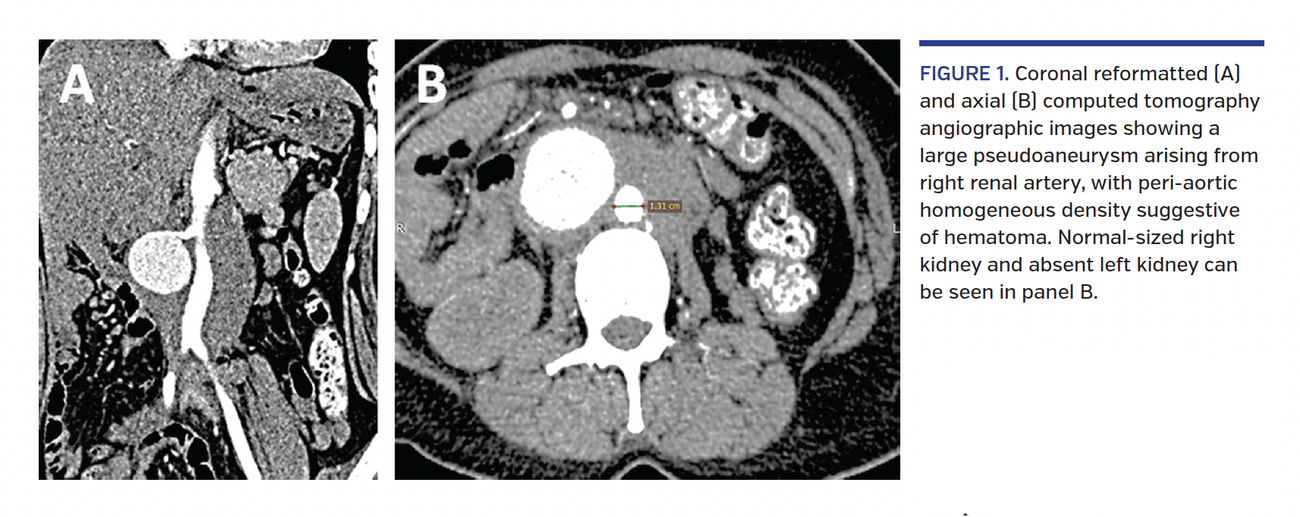

A 30-year-old woman presented with right lumbar region abdominal pain of 2-month duration. Her chronic hypertension of 13-year duration was treated medically with telmisartan, amlodipine, metoprolol, and diuretics. Abdominal exam revealed right lumbar pulsatile mass. Her serum creatinine and estimated glomerular filtration rate (eGFR) were 1.73 mg/dL and 42 mL/min/1.73 m2, respectively. Computed tomography (CT) scan revealed absent left kidney and left renal artery, normal-sized right kidney, and a large (43 x 48 mm) right renal artery pseudoaneurysm with periaortic hematoma, suggesting an impending rupture (Figure 1). Serum tests for autoimmune disease and inflammatory large cell arteritis were negative. There was no history of blunt trauma abdomen or any abdominal surgery in the past.